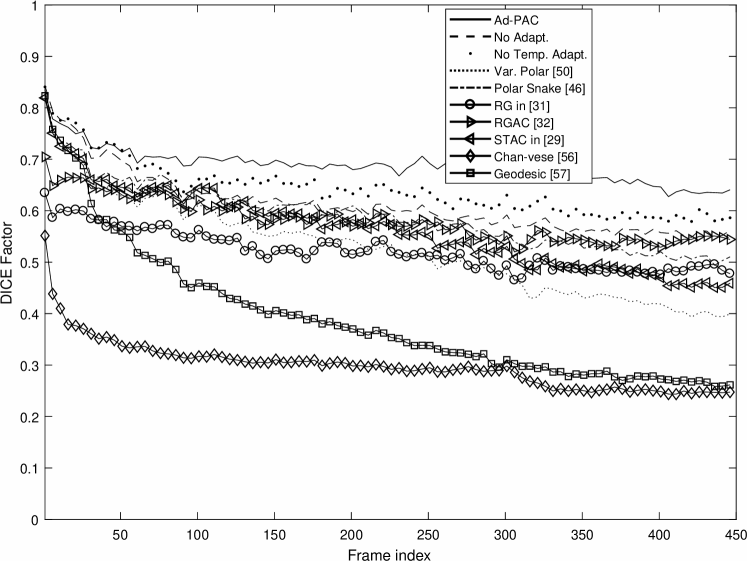

Fig. 14 presents the DICE factors obtained from each algorithm, averaged across all 65 videos irrespective of IJV shape, intensity, speed of variation and quality. From this figure, it is clear that the proposed Ad-PAC algorithm outperforms all existing algorithms with its corresponding DICE factor greater than 0.64. Other algorithms perform significantly worse. In the following sub-sections, more detailed results are presented.

V-E Influence of Image Quality

For this study, all videos were categorized, as good, average, and poor quality videos based on the blinded expert opinion. Fig. 16 illustrates the DICE results. In good quality ultrasound videos, as per Fig. 16-(a), the proposed Ad-PAC algorithm performs very close to the manual segmentation with a DICE factor consistently above 0.95. The minimum value of DICE factors for the other algorithms range from 0.91 down to 0.37 for the Geodesic algorithm [57].

In average quality videos, as shown in Fig. 16-(b), the performance of Ad-PAC algorithm drops as low as 0.65, however, it still outperforms the other AC algorithms. Poor quality videos (Fig. 16-(c)) demonstrate the minimum DICE factor as being 0.55, still above other algorithms.